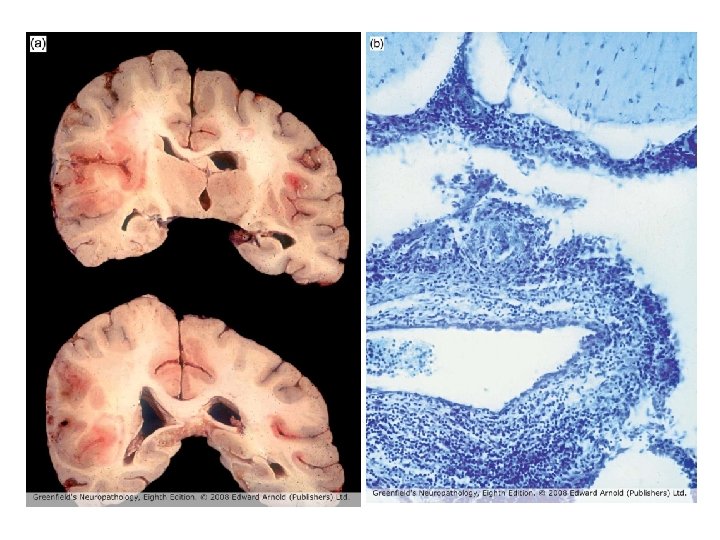

173 involved vessels 88 in grey matter, 85 in white matter Mean diameter 66. 7 ± 3. 9µm Mean ratio of wall thickness to diameter is 0. 18 ± 0. 01 Vessels < 100µm are venules/veins or arterioles/small arteries But ratio is ca. 0. 1 for venous vessels, ca. 0. 5 for arterial, so most are venous

Diagnosis • Acute vasculitis, mostly venous, in association with ulcerative colitis • Predominantly neutrophilic (acute) • Venous involvement explains the extensive hemorrhage since tissue is under arterial perfusion pressure